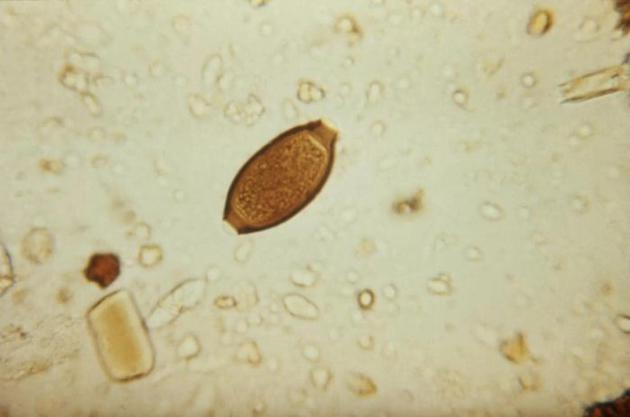

图中是一个人类鞭虫卵,目前德国一家公司希望出售猪肉鞭虫卵作为食物配料。

据美国疾病控制和预防中心数据显示,全球范围内大约有6亿人感染人类鞭虫(Trichuris trichiura),会导致人体严重缺铁和儿童发育迟缓等症状。